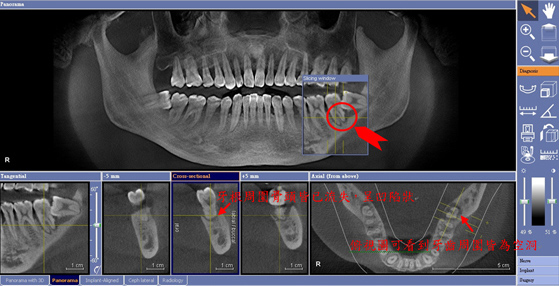

檢測智齒與神經管是否重疊

檢查水平智齒是否造成鄰牙蛀牙